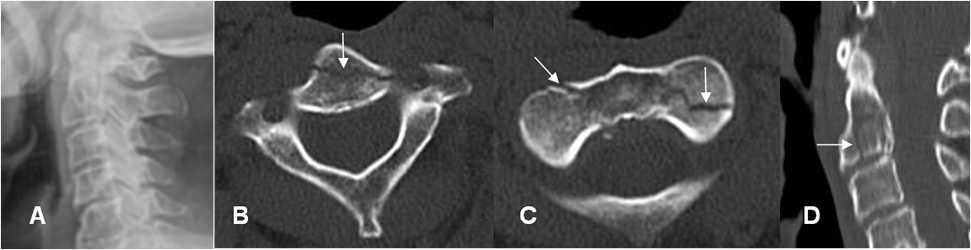

Fig 200. Fractura de Hagman.

Rx lateral. Fractura en los elementos posteriores de C2, con anterolistesis GI de C2, sobre C3.

LESIONES POR HIPEREXTENSIÓN:

Son muy comunes por un mecanismo de latigazo.

La Rx puede ser normal, por la reducción inmediata después del impacto. El ensanchamiento de la parte anterior del espacio intervertebral y la disminución del posterior, con prominencia de tejidos blandos, debe hacer sospechar esta lesión. (41). (Fig 201 A).

La avulsión asociada debe diferenciarse de fractura en lágrima, donde el fragmento suelto tiene mayor diámetro transverso, que vertical. (41). (Fig 201 B).

Fig 201 A. Lesión por hiperextensión.

A: TAC reconstrucción lateral. Incremento del espacio intervertebral anterior entre C5 y C6.

Fractura no desplazada en los elementos posteriores. (Flecha gruesa).

B: RM sagital en T2. Ruptura del ligamento intervertebral común anterior. Hiperintensidad del cordón medular, por contusión asociada. (Flecha gruesa).

Fig 201 B. Fractura por hiperextensión.

Rx lateral. Fractura en la parte anterior del cuerpo, con fragmento mas ancho, que alto.